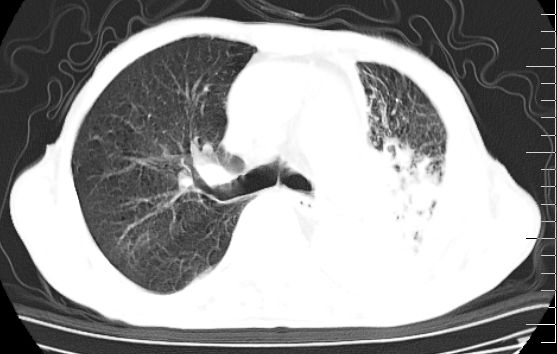

标题: CT10141:男、84岁,咳嗽、咯血1年。 [打印本页]

标题: CT10141:男、84岁,咳嗽、咯血1年。

支持左侧中央型肺癌伴下叶肺不张\\纵隔淋巴结转移.左侧包裹性胸腔积液\\心包积液.左侧少量胸腔积液..慢性支气管炎伴部分间质纤维化.

支持:左侧中央型肺癌伴下叶肺不张\\纵隔淋巴结转移.左侧包裹性胸腔积液\\心包积液.左侧少量胸腔积液..慢性支气管炎伴部分间质纤维化.另:支气管分支根部明显阻塞 狭窄,内膜凸凹不平,提示内膜增生物。

咯血病史较长,左肺下叶实变,体积未明显缩小,隐约可见血管影及坏死阴影,双肺门及纵隔淋巴结增大,心包增厚积液,纵隔右移位,单侧胸腔积液,首先考虑:大叶型肺泡癌伴纵隔心包转移。